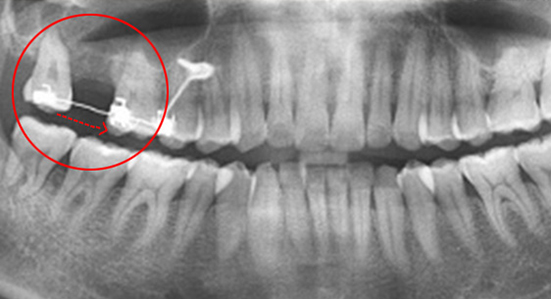

30대 남환으로 다른 치과에서 임플란트 5개 진단을 받고 내원. 교정과 협진으로 공간을 메꾸고 오른쪽 위 치아에 임플란트를 1개만 식립하여 자연치아를 최대한 활용하는 진료 계획을 세움.

다른 병원에서 임플란트 5개 진단을 받고 내원

사랑니를 빈 공간으로 이동시킴

치아가 상실된 부위 공간을 사랑니를 활용하여 모두 메워 임플란트 개수를 5개에서 1개로 감소. 또한 상실된 부위의 잇몸 뼈 높이가 높아져 예전보다 건강해 졌으며, 입술 외모가 개선되었습니다.